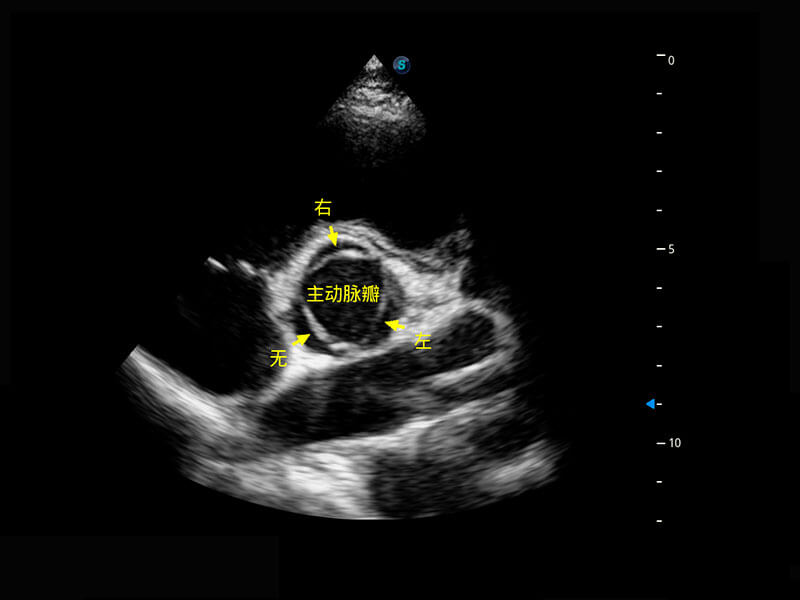

P60优异的图像质量搭载专科探头,在妇科基础疾病的诊断、卵泡生长的监测、输卵管通畅情况的判别等方面为您提供生殖应用方案。

腔内妇科-卵巢